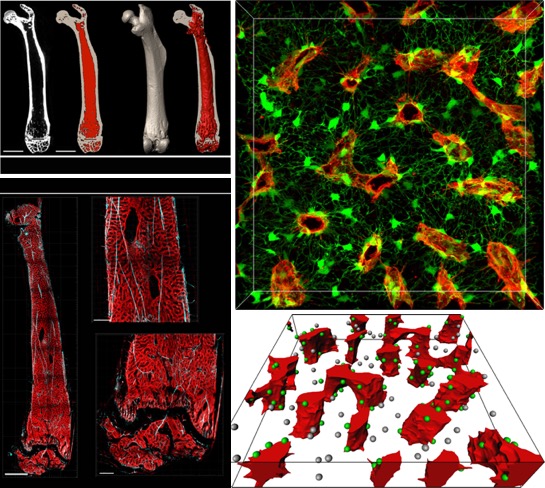

[2018] Alvaro Gomariz, Stephan Isringhausen, Patrick Helbling, Ute Suessbier, Anton Becker, Andreas Boss, Takashi Nagasawa, Grégory Paul, Orcun Goksel, Gábor Székely, Szymon Stoma, Simon F. N/orrelykke, Markus G. Manz, and César Nombela-Arrieta:

"Quantitative spatial analysis of hematopoiesis-regulating stromal cells in the bone marrow microenvironment by multiscale 3D microscopy",

Nature Communications 9(2532), Jun 2018.

[2018] Alvaro Gomariz, Stephan Isringhausen, Patrick Helbling, Ute Suessbier, Anton Becker, Andreas Boss, Takashi Nagasawa, Grégory Paul, Orcun Goksel, Gábor Székely, Szymon Stoma, Simon F. N/orrelykke, Markus G. Manz, and César Nombela-Arrieta:

"Quantitative spatial analysis of hematopoiesis-regulating stromal cells in the bone marrow microenvironment by multiscale 3D microscopy",

Nature Communications 9(2532), Jun 2018.

[2022] Alvaro Gomariz, Tiziano Portenier, César Nombela-Arrieta, and Orcun Goksel:

"Probabilistic Spatial Analysis in Quantitative Microscopy with Uncertainty-Aware Cell Detection using Deep Bayesian Regression",

Science Advances 8(5):eabi8295, Feb 2022.

[2022] Alvaro Gomariz, Tiziano Portenier, César Nombela-Arrieta, and Orcun Goksel:

"Probabilistic Spatial Analysis in Quantitative Microscopy with Uncertainty-Aware Cell Detection using Deep Bayesian Regression",

Science Advances 8(5):eabi8295, Feb 2022.

[2021] Alvaro Gomariz, Tiziano Portenier, Patrick M. Helbling, Stephan Isringhausen, Ute Suessbier, César Nombela-Arrieta, and Orcun Goksel:

"Modality Attention and Sampling Enables Deep Learning with Heterogeneous Marker Combinations in Fluorescence Microscopy",

Nature Machine Intelligence 3(9):799-811, Aug 2021.

[2021] Alvaro Gomariz, Tiziano Portenier, Patrick M. Helbling, Stephan Isringhausen, Ute Suessbier, César Nombela-Arrieta, and Orcun Goksel:

"Modality Attention and Sampling Enables Deep Learning with Heterogeneous Marker Combinations in Fluorescence Microscopy",

Nature Machine Intelligence 3(9):799-811, Aug 2021.